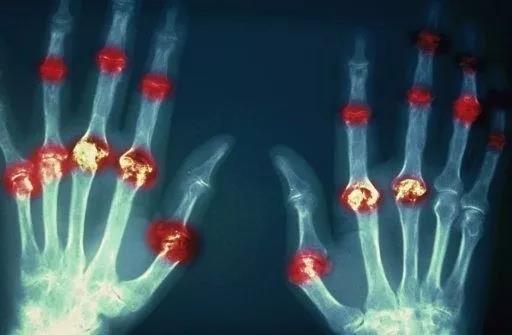

? 類風濕關節(jié)炎

類風濕關節(jié)炎是一種高度致殘的自身免疫性疾病,發(fā)病十年的患者中至少有50%的人失去勞動能力。

類風濕關節(jié)炎©Health Same of Flickr

1977年,Baldwin在用骨髓干細胞移植治療再生障礙性貧血的過程中,意外發(fā)現患者的類風濕關節(jié)炎得到緩解。

2004年,歐洲骨髓移植和抗風濕病聯(lián)盟對60例類風濕病關節(jié)炎移植患者進行回顧性分析,這些患者的關節(jié)破壞都達到不可修復程度,生活不能自理,通過干細胞移植治療后,67%的患者得到明顯緩解。

我國國內多家醫(yī)院已開展了干細胞治療類風濕性關節(jié)炎的臨床研究。首例自體干細胞移植治療類風濕關節(jié)炎在北京協(xié)和醫(yī)院完成。經過5個月隨訪,這些經常規(guī)藥物治療失敗且病情發(fā)展迅速的患者,在接受干細胞移植治療后,癥狀均獲得改善,關節(jié)腫脹消失,各項檢查指標恢復正常。

解放軍323醫(yī)院2011年的一項臨床研究中,27位患者(對照組)只使用藥物治療;另外153位患者(細胞治療組)在藥物治療的基礎上進行臍帶間充質干細胞輸注。結果顯示,治療組DAS28、HAQ 評分、ACR20較對照組下降明顯(分值越低,療效越好),Th1/Th2趨于平衡、Treg升高與臨床實驗指標及癥狀的緩解直接相關。